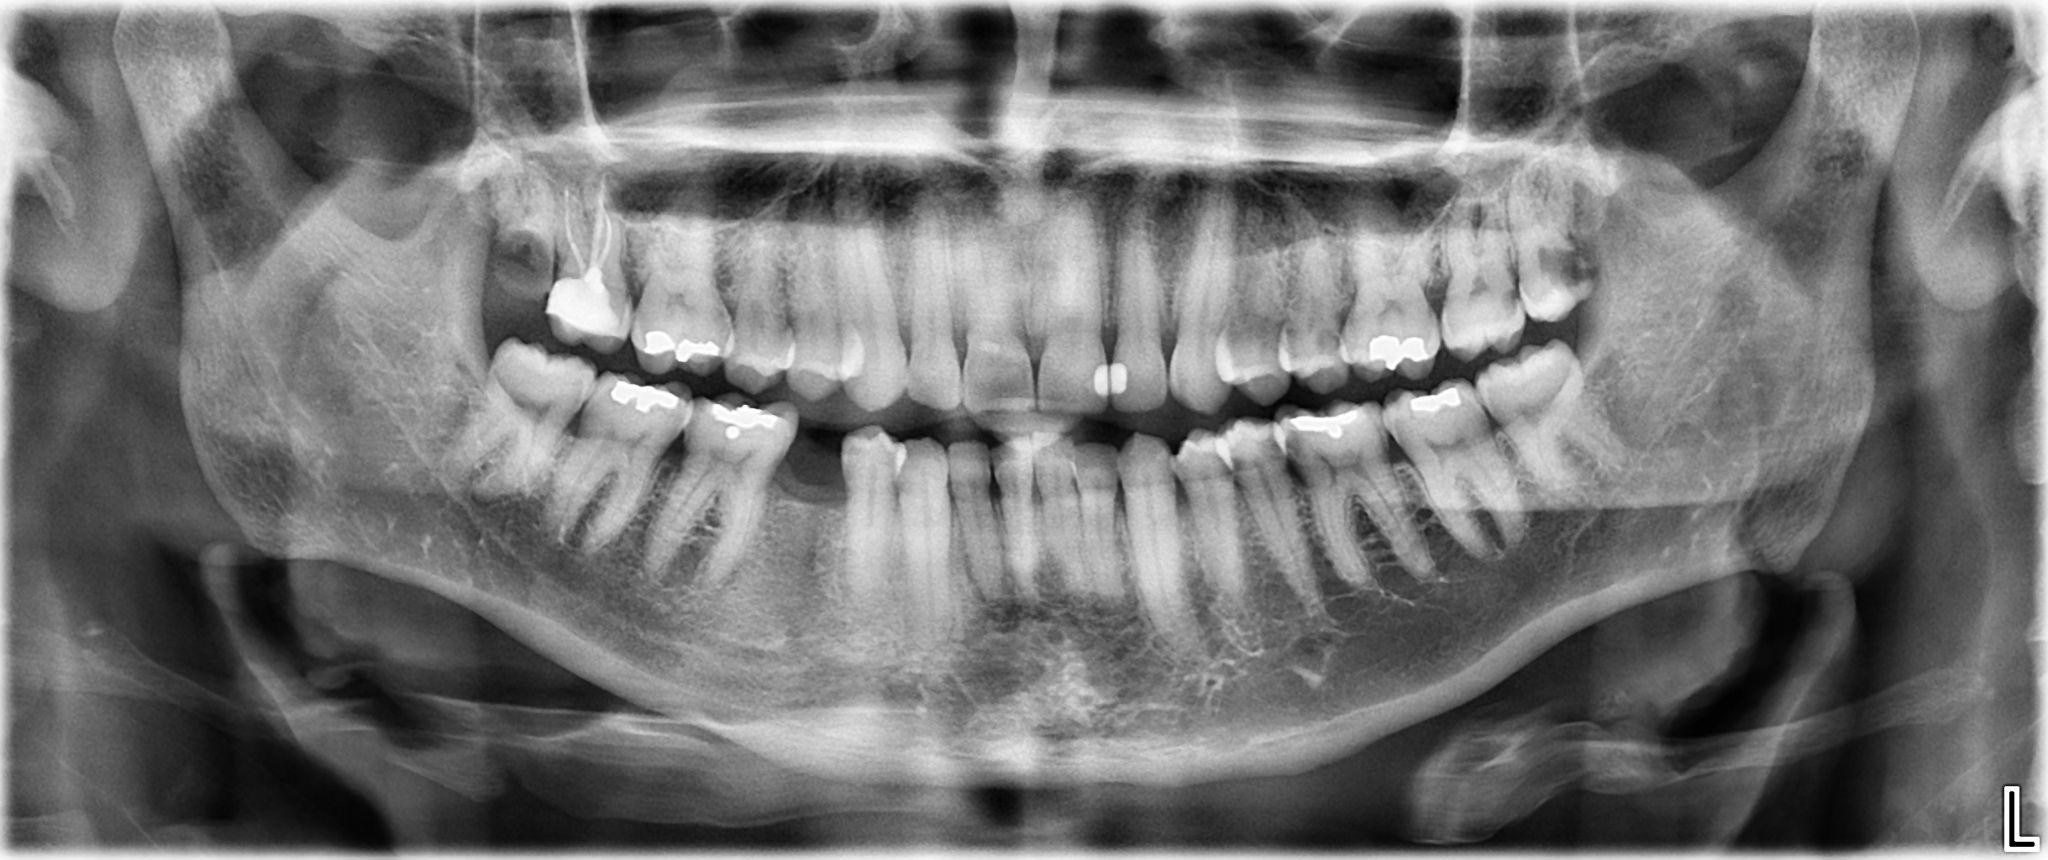

1. What options can be selected for the first quadrant of this panoramic X ray?

2 / 24

2. What options can be selected for the second quadrant of this panoramic X ray?

3 / 24

3. What options can be selected for the third quadrant of this panoramic X ray?

4 / 24

4. What options can be selected for the forth quadrant of this panoramic X ray?